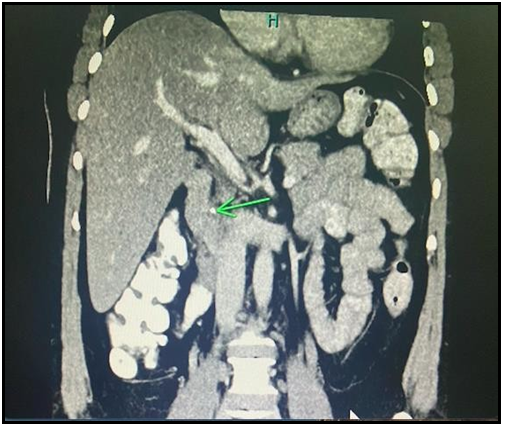

Solid pseudopapillary neoplasm of the pancreas: A report of two cases and review of the literature.